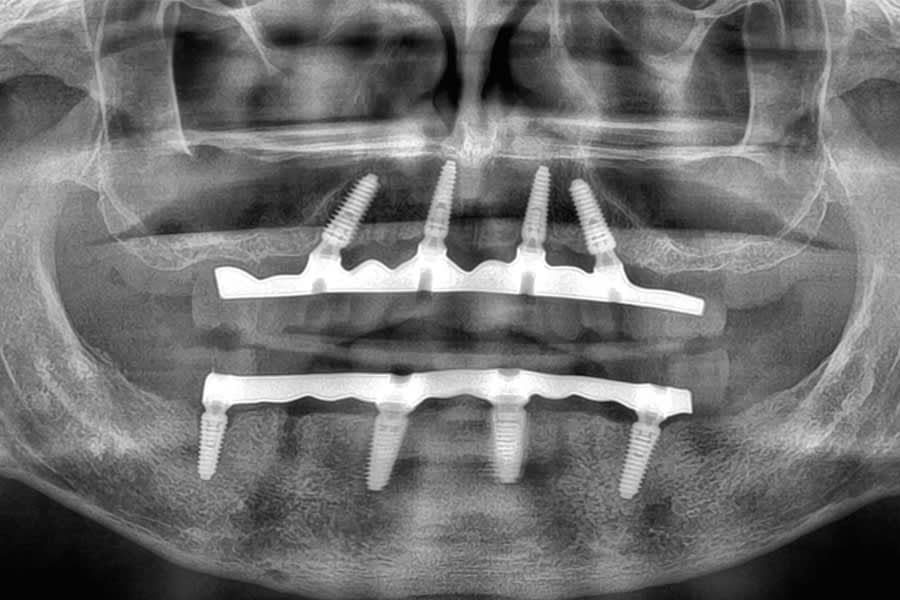

At delivery, the patient exhibited a harmonious smile, improved function, and increased confidence (Figure 31). Postoperative radiographs confirmed correct implant positioning (Figure 32). At the 6-month follow-up, peri-implant tissues remained stable, and no mechanical complications were reported.

Four implants per arch were virtually positioned using implant planning software (R2Gate®, MegaGen, imegagen.com) (Figure 7). Posterior implants were slightly tilted to maximize anteroposterior spread and reduce cantilevers while avoiding anatomic limitations such as the maxillary sinus and mandibular nerve. Screw-access emergence was controlled to ensure prosthetic retrievability and optimal occlusal positioning.